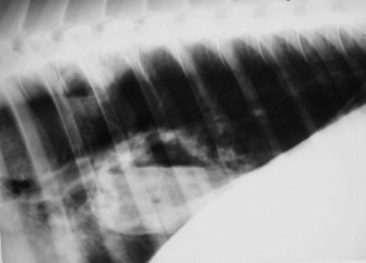

Radiography

Radiographs are indicated when the clinician suspects a congenital anomaly involving any thoracic structure; infectious disease of the pleura, pulmonary parenchyma, racheobronchial tree, or mediastinum; pneumothorax or pneumomediastinum; thoracic neoplasia of any origin; or trauma. Radiographs are frequently coupled with thoracic ultrasonographic evaluation. If significant accumulation of pleural fluid is suspected based on physical examination findings, the ultrasonographic portion of the examination should be performed first and radiographs obtained after drainage of excess fluid, as fluid may obscure potentially important parenchymal disease. The equipment needed to perform radiographic evaluation of the upper airway is available in most private practices, and most large referral and university practices have the equipment needed to perform thoracic radiography in larger patients such as adult horses and cattle. Digital radiography is becoming more commonplace and may replace more convention radiography in many practices and referral clinics over the next few years. Because of its configuration, the thorax in adult horses and cattle is filmed in the standing lateral position, generally requiring a series of three or four separate but overlapping images; thus the benefit of the ventrodorsal view in which the two lungs may be compared is lost. Neonates and small ruminants can be more readily handled and retained in recumbent positions, allowing for multiple recumbent views.

Radiographic assessment of the thorax of large animals remains preferable to ultrasonographic examination for detection of diffuse parenchymal diseases such as interstitial pneumonia, pulmonary edema, equine multinodular pulmonary fibrosis (EMPF), fungal pneumonia, acute lung injury (ALI), acute respiratory distress syndrome (ARDS), chronic disorders, and deep parenchymal or mediastinal abscesses. Unfortunately, many radiographic changes in equine respiratory disorders tend to be nonspecific or, in certain disease such as EIPH, inflammatory airway disease (IAD), or heaves, minimal to nonexistent.

Four types of radiographic patterns are described for the thorax: alveolar (airspace), interstitial, bronchiolar, and vascular. Opaque areas coalesce and fully obliterate vessels and bronchi in the alveolar pattern; air bronchograms may be prominent. This pattern is common in pulmonary edema, pulmonary hemorrhage, EMPF, ALI, ARDS, lung consolidation, and neoplasia. Interstitial patterns are the most common patterns noted in equine thoracic radiographs and are characterized by a blurring of the edges of pulmonary vessels, a diffuse increase in lung density, and variable reticular, linear, and nodular opacities. The reticular pattern is most commonly associated with more diffuse infectious lung diseases, pulmonary edema, interstitial pneumonia, and pulmonary fibrosis, whereas the irregular linear pattern is seen most commonly with resolving bronchopneumonia. A nodular pattern is seen with abscesses, granulomata, and neoplasms. It is rare to see a pure bronchial pattern in a horse, and it usually seen in association with an interstitial pattern. An exception is paired linear opacities or numerous small circular opacities (donuts) representing thickening of large or medium airways in equine bronchitis and bronchiolitis. The vascular pattern is seen in horses radiographed immediately postexercise or in animals with left-to-right cardiac shunts. Finally, extraparenchymal problems such as pleural effusions or free gas may be seen on thoracic radiographs of large animals. Thoracic radiology may be used for evaluation of potential rib fracture but is far less sensitive than thoracic ultrasonography in this regard.